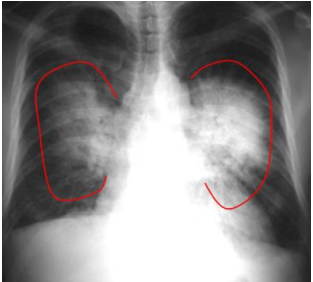

Observe a radiografia, abaixo:

Acima, temos uma radiografia frontal de paciente portador de insuficiência cardíaca congestiva. Observa-se aumento da área cardíaca e consolidações bilaterais com padrão de “asa de borboleta”, que indica: